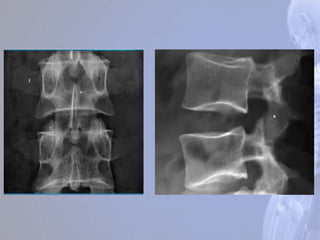

Região Lombar (LI– LV) São as maiores e mais fortes da coluna. Processo espinhoso bem adaptados para a fixação dos músculos do dorso

T1 sagital T2 sagital

Listese L4-L5

degenerativa